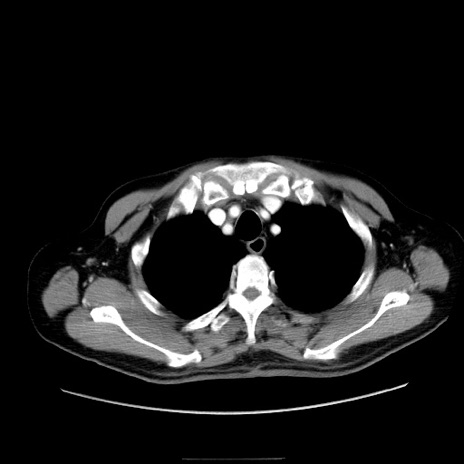

症例30(横断像)

【症例】80歳代男性

【主訴】臍周囲痛

【現病歴】約6時間前から臍下部痛が出現。次第に腹部膨隆・背部痛も生じてきたため来院。背部痛の場所は変化しない。

【身体所見】意識清明、BT 36.3℃、BP  131/87mmHg、P 87bpm、SpO2 100%(RA)、臍周囲自発痛・圧痛あり、反跳痛なし、自発痛部位に一致して板状硬あり、腹部膨隆、腸雑音減弱、CVA tenderness両側陰性。

【データ】WBC 19600、CRP 0.33